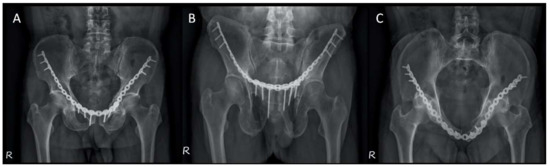

- Hung, C.C.; Li, Y.T.; Chou, Y.C.; Chen, J.E.; Wu, C.C.; Shen, H.C.; Yeh, T.T. Conventional plate fixation method versus pre-operative virtual simulation and three-dimensional printing-assisted contoured plate fixation method in the treatment of anterior pelvic ring fracture. Int. Orthop. 2019, 43, 425–431. [Google Scholar] [CrossRef] [PubMed]

- Hsu, C.L.; Chou, Y.C.; Li, Y.T.; Chen, J.E.; Hung, C.C.; Wu, C.C.; Shen, H.C.; Yeh, T.T. Pre-operative virtual simulation and three-dimensional printing techniques for the surgical management of acetabular fractures. Int. Orthop. 2019, 43, 1969–1976. [Google Scholar] [CrossRef]